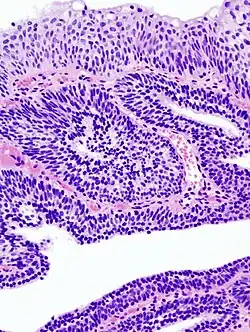

Photomicrographie d'un papillome malpighien sur une langue. Coloration à l'hématoxyline et à l'éosine.